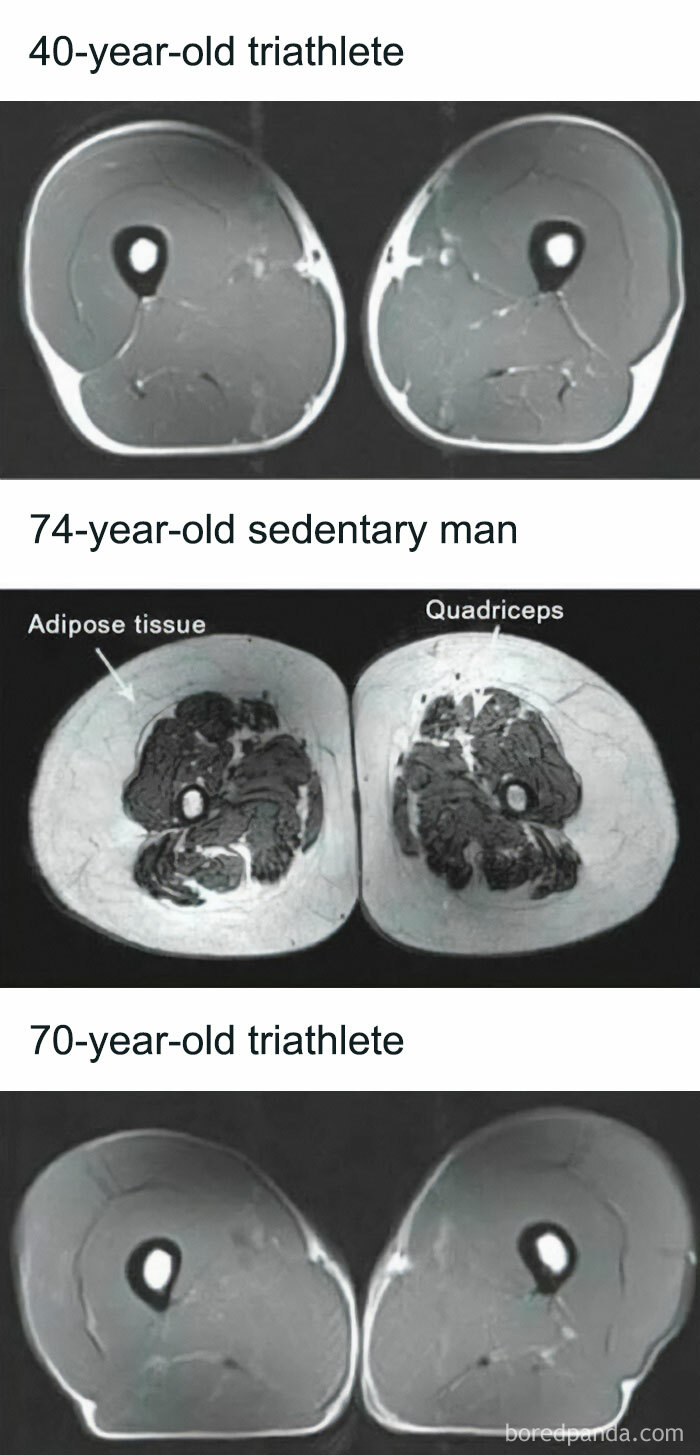

Differences In Muscle Mass

This study looked at how exercise can preserve muscle mass. Here they compare a 74-year old sedentary man and a 70-year old triathlete, and the difference in fat and muscle tissue is extreme